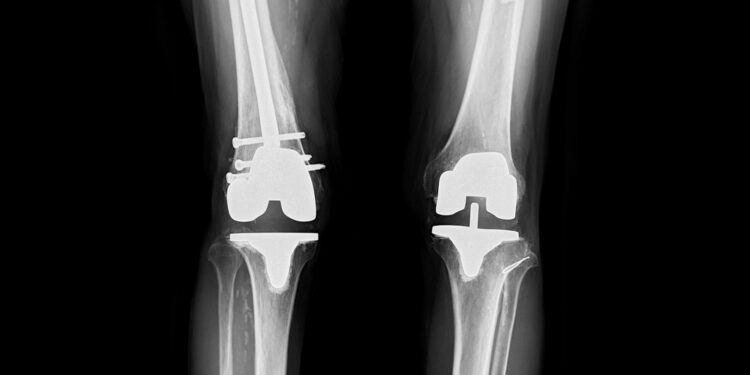

Prireikus operacijų, dažniausiai jos atliekamos norint sumažinti galūnių ilgio skirtumą. Kartais operuojant galima pailginti trumpesnę galūnę arba sulėtinti greičiau augančios galūnės augimą. Jei siūlomas chirurginis gydymas, svarbu aptarti jo tipus ir eigą su gydytojų komanda.